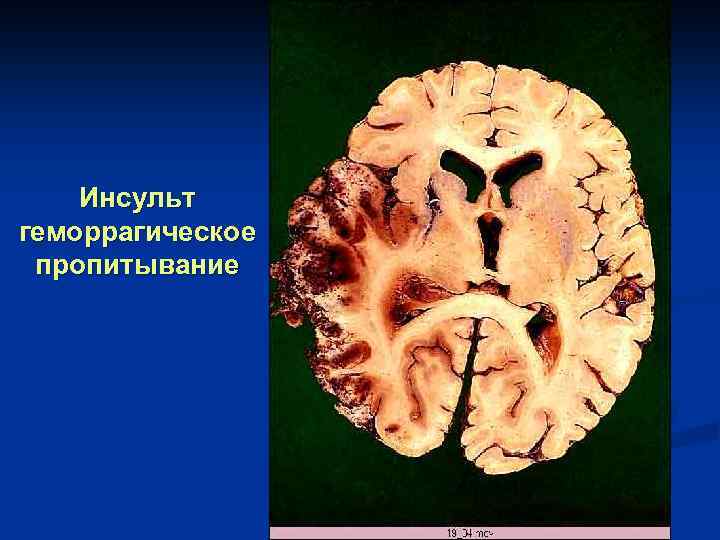

Инсульт (красное размягчение мозга) гематома

Инсульт геморрагическое пропитывание